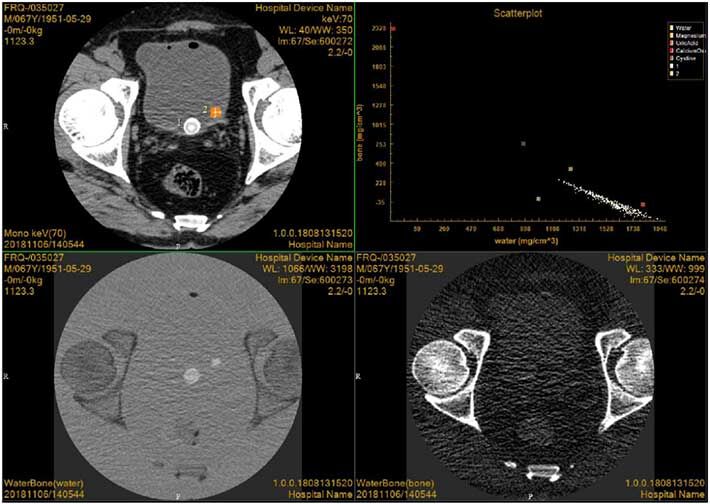

3)Dual-energy platform

YSCT-128C equipped the maturest sequence tomography technique, that is, the CT imaging system does not change, but adopts two rotatory scanning imaging, one rotation with higher kVp (e.g.,140 kVp) and one with lower kVp (e.g.,80 kVp). The two-domain spatial registration of two-time imaging data in data domain and image domain ensures the homology, homodomain and simultaneous imaging of dual-energy.

Case presentation: This patient was a 67-year-old man with many years of bladder calculi. Image showed two large (1) small (2) stones in the bladder, and the main components of the stones were determined as uric acid by scatter plot. At the same time, calculi were found in the water diagram but not in the bone diagram, which was also consistent with the characteristics of uric acid calculi.